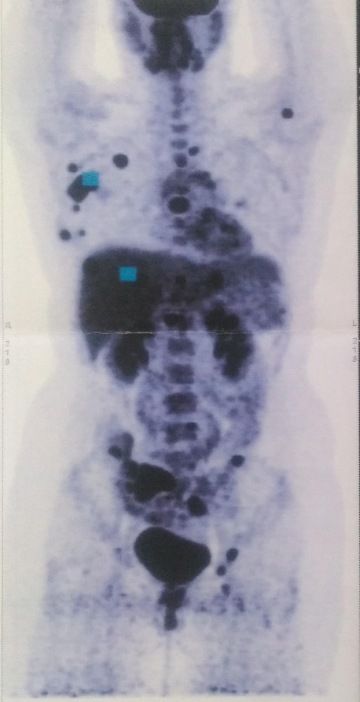

Na PET/CT neboli petko, jsem šla za pár dní, i když čekačka je za normálních okolností týdny. Výsledky byly poměrně rychle, a tak už jsem zase seděla v čekárně. Zavolání, příchod, židle, pár slov a zastavil se čas. „Bohužel máte metastáze v uzlinách, játrech a v kostech, hlavně v pánvi, rukou, lopatkách, páteři...“ CO TEĎ?! Smířená s rakovinou jsem byla, ale ne v takovém rozsahu. Nikdo nechápal a do dnešního dne nechápe, jak je to v mém věku možné.

Nádor mám hormonálně pozitivní, jak ráda říkám, to nejlepší z nejhorších. Tudíž podstupuji hormonální terapii, každý měsíc injekce pro blokádu hormonů, plus léky. Zhruba po každých 5 měsících chodím na petko, aby se zjistilo, jak léčba funguje nebo nefunguje. První léky mi fungovaly asi rok a čtvrt, játra a uzliny byly čisté, kosti stejné. Druhé, brala jsem je 6 měsíců, nefungovaly vůbec. Zase mi začala svítit játra, jedna uzlina, a tak jsem v prosinci 2021 dostala chemošky. Jak se jim říká v onko světě – Oranžády, Aperol... bleh. Díky bohu jsem je zvládla bez jediného zvracení. Po nich jsem v dubnu dostala další chemoterapie, které byly v pilulkách, ty jsem brala až do března letošního roku. Na petku se zase ukázaly nějaké dvě malé potvůrky v prsu. Nevadí. Jedeme dál. Mám novou léčbu a věřím, že zase nějaký ten rok bude fungovat. Dokud je léčba není nic ztraceno. Byly dny, které jsem probrečela, zvláště čerstvě po diagnóze, říkala si, co jsem udělala špatně, proč já, jsem mladá, nic jsem ještě neprožila... patří to k tomu vyrovnání se s nemocí. Další psychický propad jsem měla zhruba 1,5 roku po diagnóze. Měla jsem spoustu volného času a moje hlava si dělala co chtěla. Měsíc jsem byla mimo. Připadala jsem si na obtíž. Nakonec jsem musela zvednout zadek z postele a postavit se tomu. Pomáhaly mi dlouhé procházky, povídala jsem si sama se sebou a dodávala si sílu, křičela, když bylo třeba. Vyhledala jsem i online psychologa, což bylo skvělé rozhodnutí.